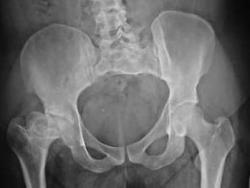

Several consumers who had Wright Conserve hip replacement surgery have filed product liability lawsuits against Wright Medical Technology, Inc. All federal lawsuits will be transferred to one judge for multidistrict litigation (MDL) as ordered by a panel of federal judges.

The Food and Drug Administration approved the use of hip replacements in November of 2009. The Wright Conserve hip replacement system was approved through the FDA’s 510(k) program, which allows companies to market similar products without patient testing.

Shortly after the hip replacement was approved, the FDA received more than 200 reports alleging negative events that occurred after having hip replacement surgery.

According to claims reported to the FDA, metal parts of the acetabular cup have the tendency to rub against each other and shed metal particles into the body, which causes the device to loosen and fail.

It also causes metallic debris to build up in the body’s soft tissues, which causes an increased cancer risk.